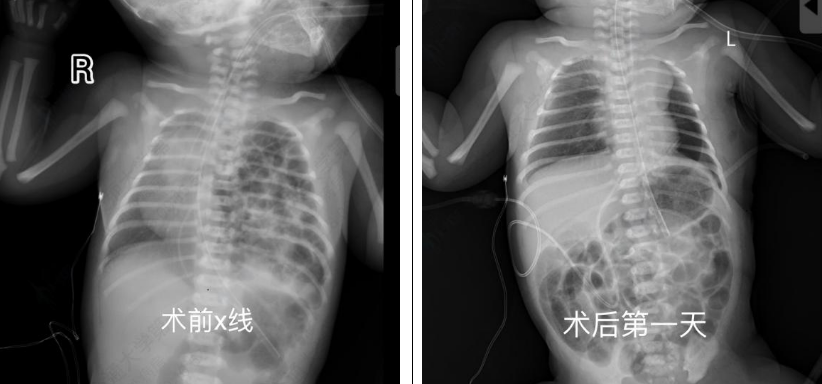

出生后 24 小时,患儿病情逐渐趋于稳定,但影像学提示脾脏、肠管仍大量疝入胸腔,肺组织明显压缩,有可能发生肠绞窄或感染性休克,危及患儿生命。经综合评估,依据胎儿先天性膈疝临床管理指南(2022),儿外科团队决定实施胸腔镜下膈疝修补术 [2]。手术过程中可见脾脏及肠管几乎占据整个胸腔,造成肺组织严重受压。新生儿脾脏组织异常脆弱,稍微牵拉或触碰即可导致出血,且止血困难,因此操作需慎之又慎。在充分暴露后,曹主任小心翼翼地将腹腔脏器全部还纳后,随即对膈肌缺损进行修补,每一针都精准缝合,避免出现缝隙导致再次疝入,由于缺损面积巨大,无法直接采用折叠缝合方式关闭,因此使用生物补片行加固修补。在麻醉科和手术部护理团队的精密配合下,儿外科团队成功将脏器还纳腹腔并精准修补膈肌缺损,手术顺利完成。术后患儿肺扩张逐渐恢复,呼吸功能改善,成功撤离呼吸机。目前状态良好,已顺利出院。